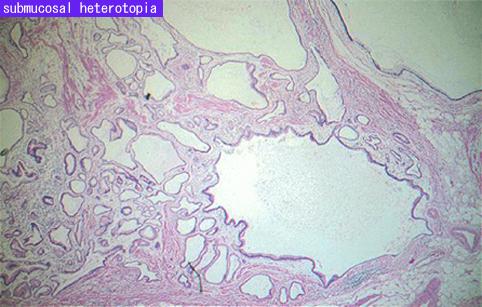

질환(병리주체)의 분류 악성 상피성종양/선암

검사방법 마이크로